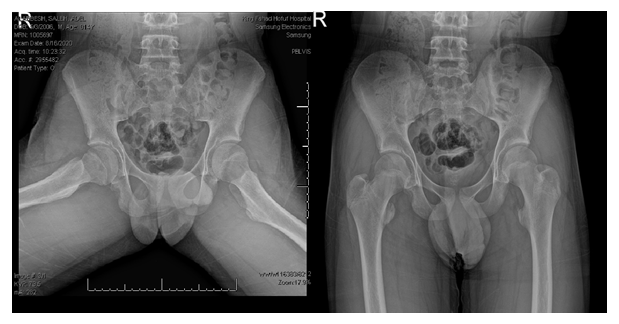

The anterior- posterior view of pelvis X ray show avulsion fracture of right lesser trochanteric (Figure 1 & 2). We suggested non-operative treatment for the patient which include analgesics and non-weight bearing for 4 weeks with use of axillary crutches followed by partial weight bearing as tolerated. The patient was discharged and was followed up regularly in clinic with repeat plane pelvic x-rays.

Figure 1 X-ray taking for the pelvis in anterior-posterior view shows displaced right isolated lesser trochanter fracture.